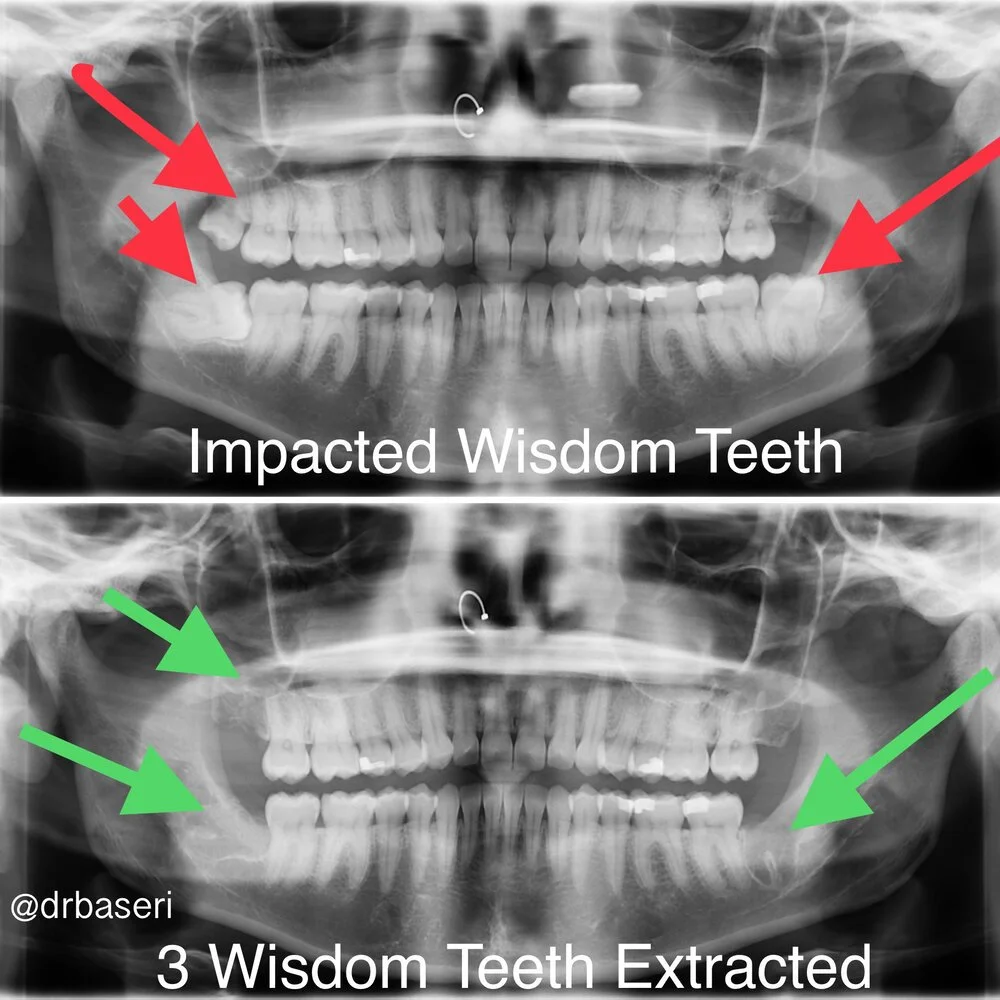

Wisdom teeth (third molars) usually erupt between ages 17–25. In many mouths, there simply isn’t enough room, so they get impacted, come in at an angle, or only partially break through the gums. When that happens, they can:

Expertise with complex, impacted wisdom teeth

⭕️ Advanced CBCT 3D imaging for safer surgery

We use cone beam CT (CBCT) to create a 3D map of your wisdom teeth, roots, nerves, and sinuses. This lets us: